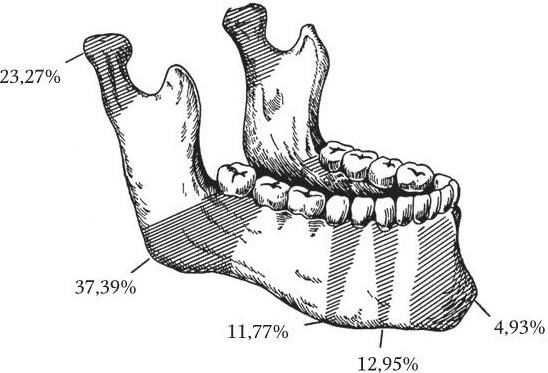

Неогнестрельные переломы нижней челюсти, чаще всего «линейные», проходят в «местах слабости»: в области центральных резцов, клыка и подбородочного отверстия, угла нижней челюсти, мыщелкового отростка (рис. 2). Около 75 % переломов происходят в пределах зубного ряда и являются, как правило, открытыми (инфицированными). При смещении отломков интимно связанная с надкостницей слизистая оболочка десны практически всегда разрывается в месте перелома и зона повреждения инфицируется за счет содержимого полости рта.

Рис. 2. «Места слабости» и частота неогнестрельных переломов нижней челюсти по локализации